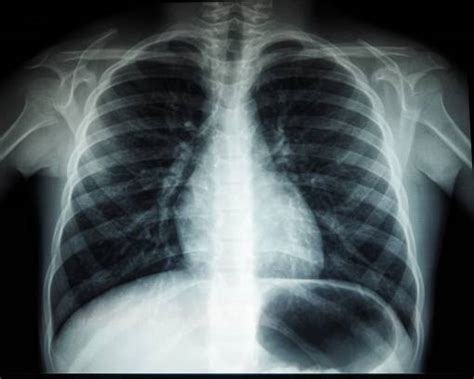

Radiografie pulmonară

Radiografia pulmonară este o investigație recomandată tuturor pacienților care acuză simptomul de dispnee. Această investigație este foarte frecventă pentru că permite vizualizarea inimii, plămânilor, căilor respiratorii, identificarea lichidului la plămâni.

Diagnosticul de pneumonie în sarcină se bazează pe o combinație între evaluarea clinică și cea imagistică. Radiografia toracică rămâne standardul de aur pentru confirmarea pneumoniei, însă doza de radiații trebuie semnificativ redusă.